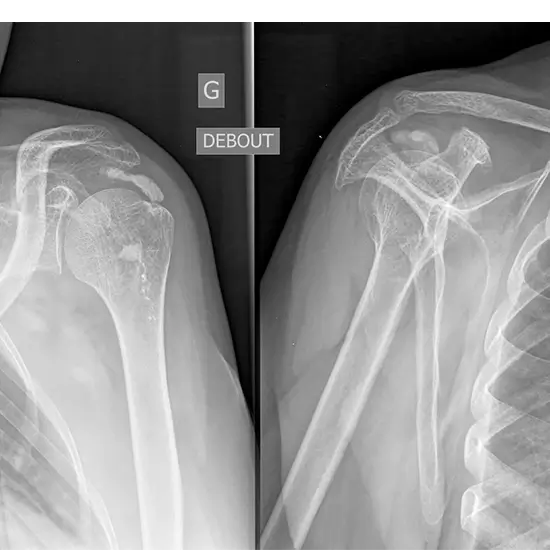

What is an X-ray Right Shoulder Joint AP and Axial View Test?

This test examines the shoulder. The shoulder area contains the shoulder joint, collar bone, shoulder blade, upper arm bone, and surrounding soft tissues.

• This method finds fractures, infections, abnormal growths, dislocated joints, or a frozen shoulder. It can also track how well a patient is healing after surgery.

• This imaging method can find cysts, tumors, osteoporosis, bone deformities, glenohumeral instability, and glenohumeral instability.